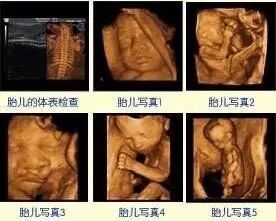

9.能自动为胎儿进行宫内拍“写真”和动态录像。

这个时期的准妈妈可以看到宝宝的脸部、口唇、鼻子等,有时能见到胎儿吮手动作。